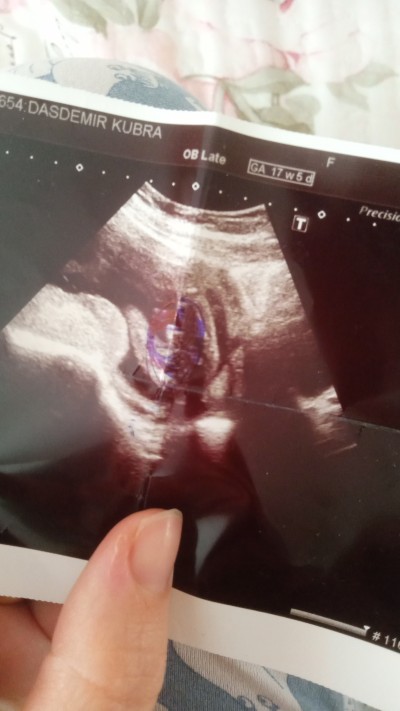

Çokk çokk nadirdir heralde canim detaylida mutlaka gözükürdü zaten. Ben detaylida oglumu çişini yaparken gördüm. Birde cinsiyet öğrendiğimde doktor resmen pipisinin fotosunu verdi bana dur buraya atayim hatta :)) Kalemle yuvarlak icine almis :D

image